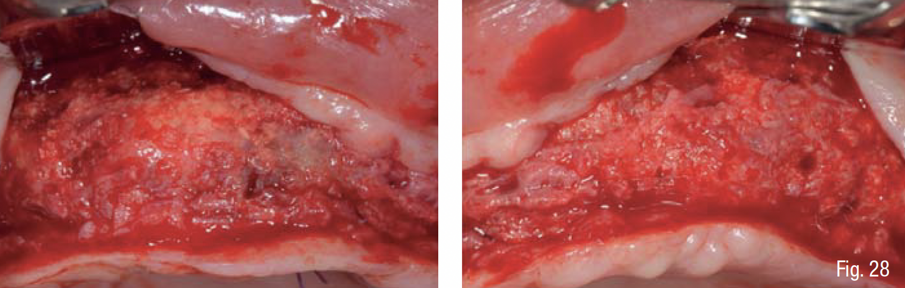

Durante la fase di chirurgia implantare, è stata inizialmente fissata la dima chirurgica sfruttando l’appoggio dento-mucoso; successivamente, è stata eseguita un’incisione lineare crestale e si è proceduto al sollevamento di un lembo vestibolare a tutto spessore e alla rimozione delle mini-viti e della griglia, che essendo osteointegrata in diversi punti è stata rimossa in diversi frammenti. La percentuale di rigenerazione, ovvero il rapporto tra il volume osseo rigenerato e il volume osseo pianificato, è stato calcolato essere del 96% (Figg. 25-29). La dima chirurgica è stata riposizionata e fissata nuovamente mediante i pin di fissaggio precedente preparati, non avendo più il supporto mucoso. Usando una tecnica di sotto-preparazione, sono stati realizzati i siti implantari e sono poi stati inseriti i 6 impianti programmati: 4 impianti dritti con dimensione 10 x 3.7 mm e 2 impianti angolati a 25° con dimensione 12 x 3.7 mm, al fine di evitare il seno mascellare (BTK implant Isy+, Biotec Srl, Dueville, Vicenza, Italy) (Fig. 30).